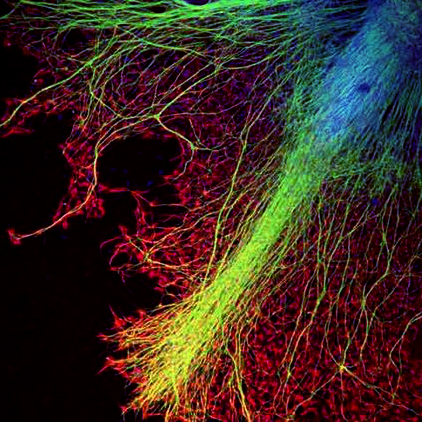

Myoblasts and Fibroblasts

Muscle derived cells, mainly myoblastes and fibroblasts are cultured in monolayers. Immediately after myoblaste fusion, whole transverse slices rat embryos spinal cords with dorsal root ganglia attached are placed on the muscle monolayer. After 24h neuritis are observed growing out of the spinal cord explants. They make contacts with myotubes and induce the first contractions. Quickly thereafter, innervated muscle fibres located in proximity to the spinal cord explants, are virtually continuously contracting (see movies on our website). Innervated fibres are morphologically and spatially distinct from the non-innervated ones and could easily be distinguished from them

(Askanas et al., 1987) .